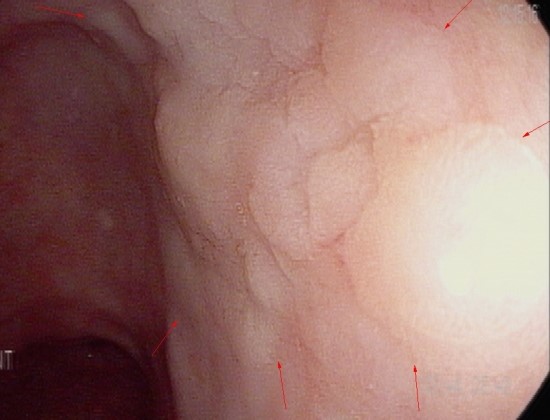

검진 위내시경시 약 2cm의 granular mucosal change가 위 전정부 후벽에 관찰

조직검사상 고등급의 이형성을 보이는 선종

Stomach, antrum, posterior wall, ~ angle, posterior wall, endoscopic biopsy;

Low grade dysplasia and focal high grade dysplasia

* Special stain result; Giemsa stain for H.pylori; Negative(-) (No bacilli)

고등급의 이형성 동반시 점막하 절제로(ESD) 전체 절제시 위암으로 진단되는 경우는 30%

4년전 동일 부위에 화생성위염이외 결절성 병변은 관찰되지 않음. 이후 검사는 시행하지 않음.

화생성 위염(장상피 화생) 소견 있을 시 1년마다 검사할 것을 추천함.

장형위암의 경우 초기 변화/진행이 늦을 수 있는데 장상피 화생이 있으면 1년마다(최대한 2년)마다 검사를 해야 조기 진단에 도움이 될 것으로 사료됨.